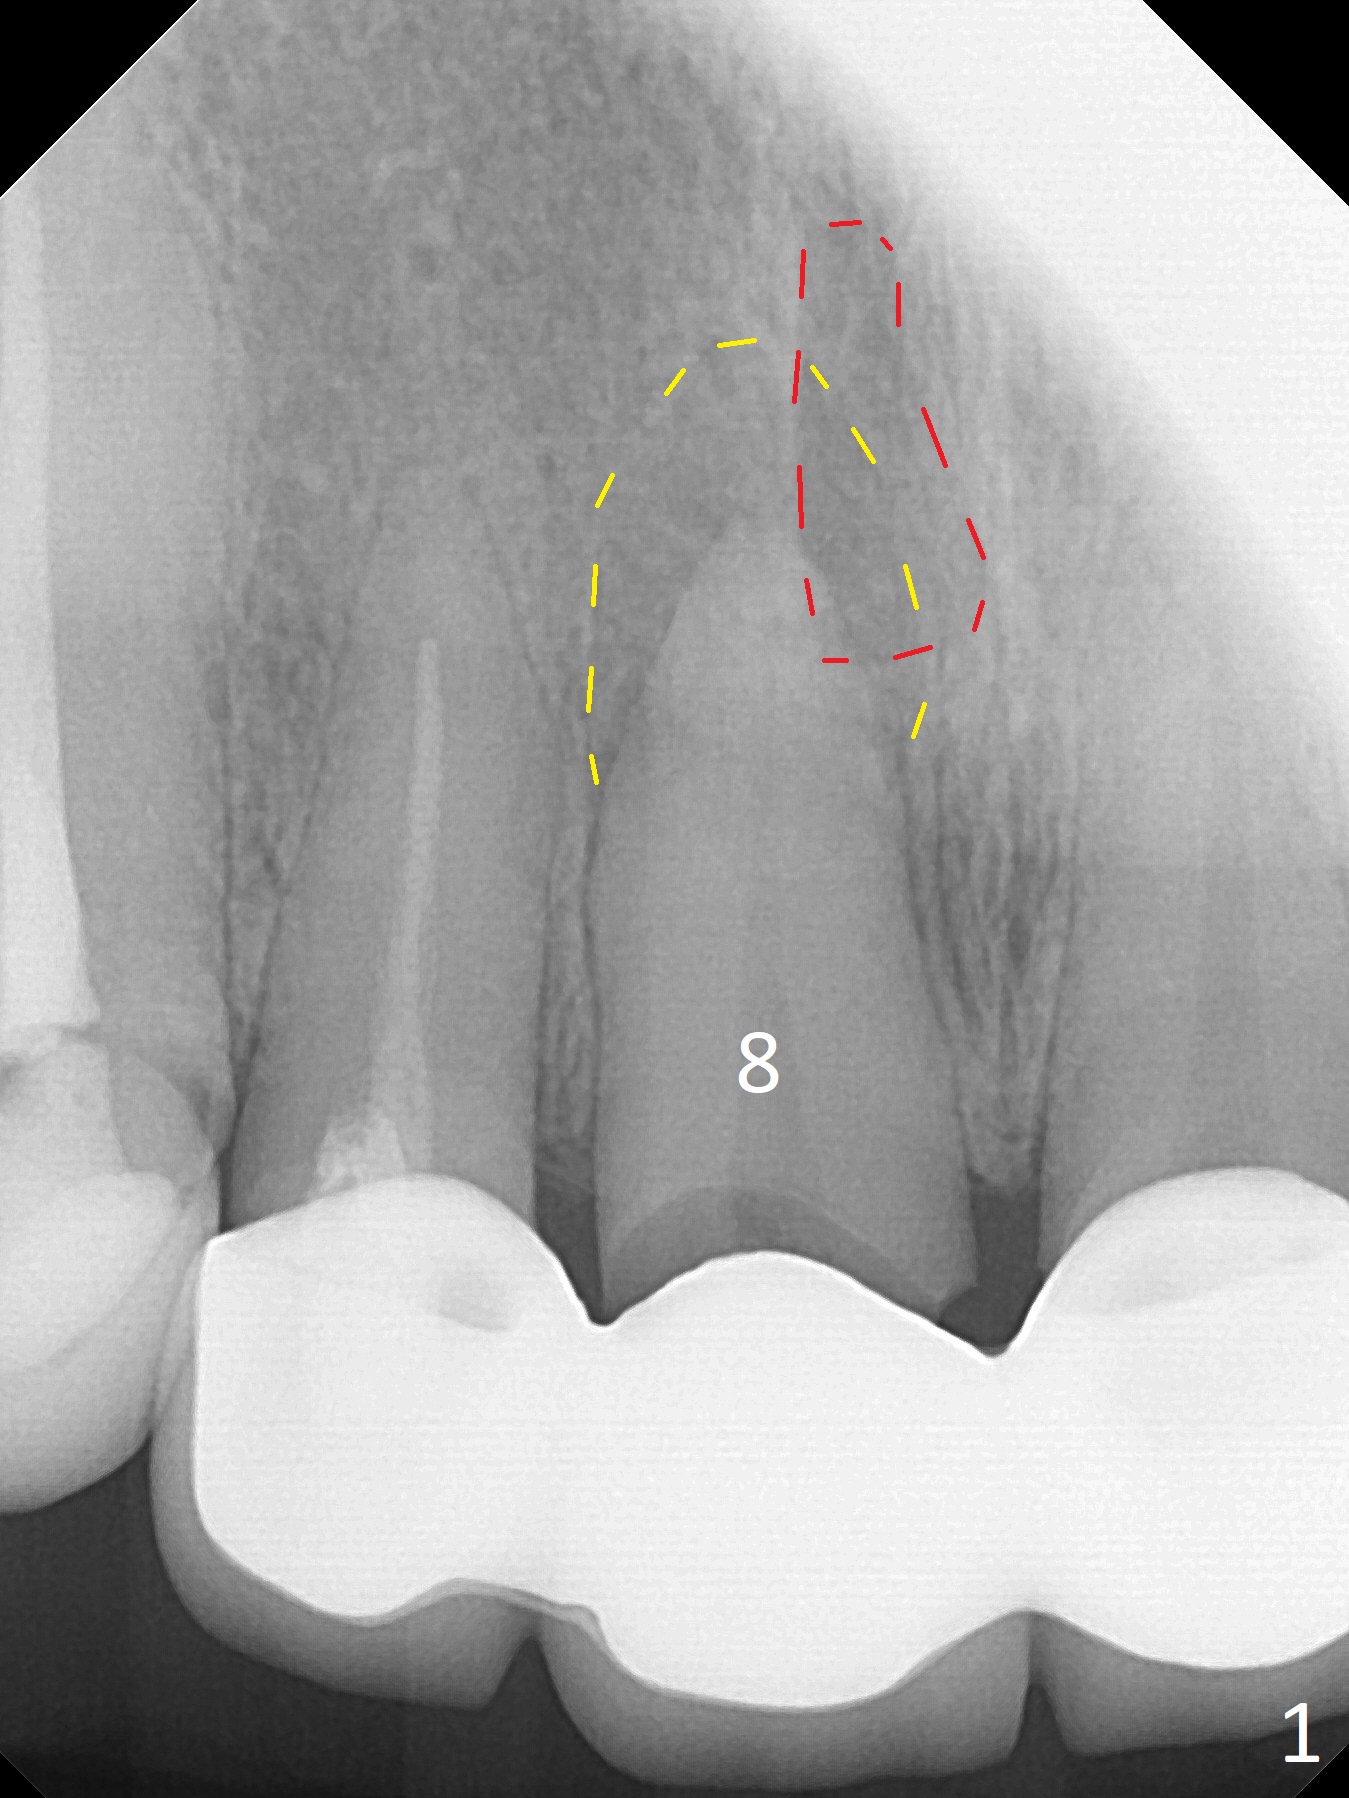

A 55-year-old woman develops apical abscess (Fig.1 yellow outline) at #8 following #7-9 FPD fabrication in China. Since the Incisive Foramen (red outline in Fig.1) is large, initial osteotomy and implant placement will be established not only as palatal as possible, but also mesial (Fig.2 green). IBS system is chosen for this case, because of its 4 mm abutment (minimal prep for provisional), as compared to UF (4.5 mm) and SM (3.9 and 4.8 mm for narrow, 4.8 mm for regular). However, the narrowest and longest IBS implant is 4x13 mm (Fig.2); it barely passes the apical lesion. The 2nd narrowest and longest FC implant is 4.5x15 mm (Fig.3, metal may show off unless subcrestal), as compared to UF (3.8x18 mm, Fig.4) and SM (3.8x14 mm). If the trajectory and osteotomy is initiated ideally, use IBS. Otherwise switch to UF. The FPD will be sectioned.